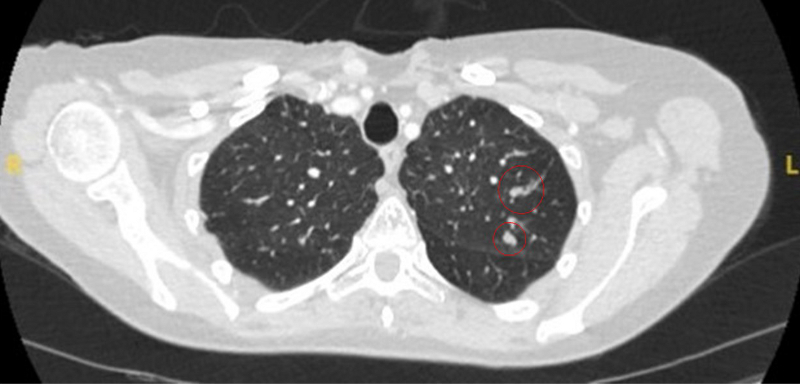

Tomografia computadorizada (TC) mostrando dois nódulos periféricos no lobo inferior esquerdo (um ligeiramente espiculado e outro com margens mais lisas) em paciente com febre, marcadores séricos inflamatórios elevados e hemoculturas confirmando Streptococcus intermedius. Ambos os nódulos foram completamente resolvidos após um ciclo de linezolida, condizente com êmbolos sépticos

Do acervo de Dr. George Tsaknis, MD, PhD, FRCP (Londres), MRQA, MAcadMEd, PGCert; usado com permissão